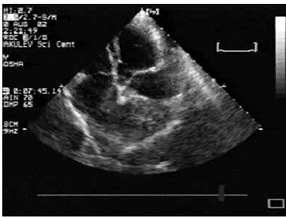

) Эхокардиография. Испытуемой группе собак

сделали ЭКГ снимки на которых можно проследить : увеличение левых отделов

сердца , увеличение левого и правого желудочка , растяжение и деформация

створок митрального клапана ,в некоторых случаях застойные явления в легких . У

каждой собаки степень недостаточности митрального клапана на фоне эндокардиоза

была разная но симптомы у всех 30 овчарок были схожими : одышка , усталость ,

отказ от еды , кашель . На основе полученных снимков ЭКГ можно наблюдать

различные стадии развития болезни (рис 7,8).

Рис 7. недостаточность митрального клапана, Рис

8. увеличение левых увеличение размеров левого предсердия. левых отделов